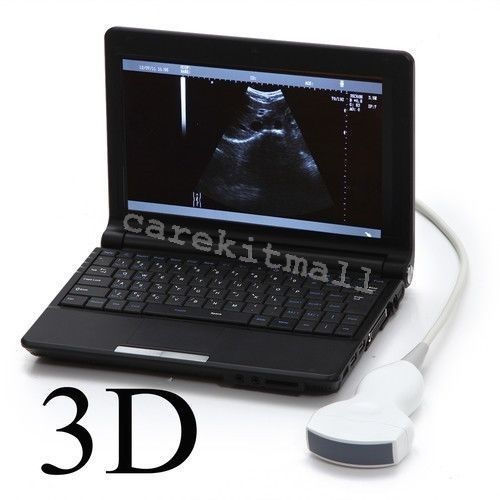

Explore the Benefits of the 10.1'' Ultrasound Scanner

monitor: 10.1â high-resolution TFT LCD

Enhanced Imaging Quality

The 10.1'' Ultrasound Scanner stands out for its superior imaging quality, making it an essential tool in medical diagnostics. It utilizes advanced technology to deliver clear and detailed images of internal organs, which is crucial for accurate diagnoses. When healthcare professionals have reliable imaging, they can make informed decisions about patient care. This scanner includes Convex, Linear, and Transvaginal probes, allowing for versatility in various medical scenarios.

User-Friendly Interface

With its intuitive design, the Ultrasound Scanner ensures that medical staff can operate it efficiently. The large 10.1'' display provides an easy view of the imaging results, which enhances the workflow in busy clinical environments. Moreover, it is equipped with a thermal recorder, enabling practitioners to save and print images directly during examination. This user-friendly interface reduces the learning curve, so professionals can focus on providing the best care for their patients.